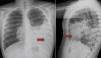

Varón de 10 años, previamente sano, que debuta con un cuadro de tos no productiva y dolor torácico de un mes de evolución. Con la sospecha diagnóstica de neumonía atípica es tratado con claritromicina durante 10 días sin mejoría. Se le realiza una radiografía (fig. 1) donde se le diagnostica de neumonía complicada con empiema. Lo derivan a nuestro hospital para tratamiento y drenaje del empiema.

A su llegada, a la auscultación se aprecia una disminución del murmullo vesicular en hemitórax izquierdo y ruidos hidroaéreos dispersos. Tras revisar las imágenes, se realiza una ecografía y tomografía axial computarizada (figs. 2 y 3) observándose parte del intestino delgado y colon izquierdo intratorácicos. El diafragma izquierdo no se visualiza. El diagnóstico es compatible con una hernia diafragmática.